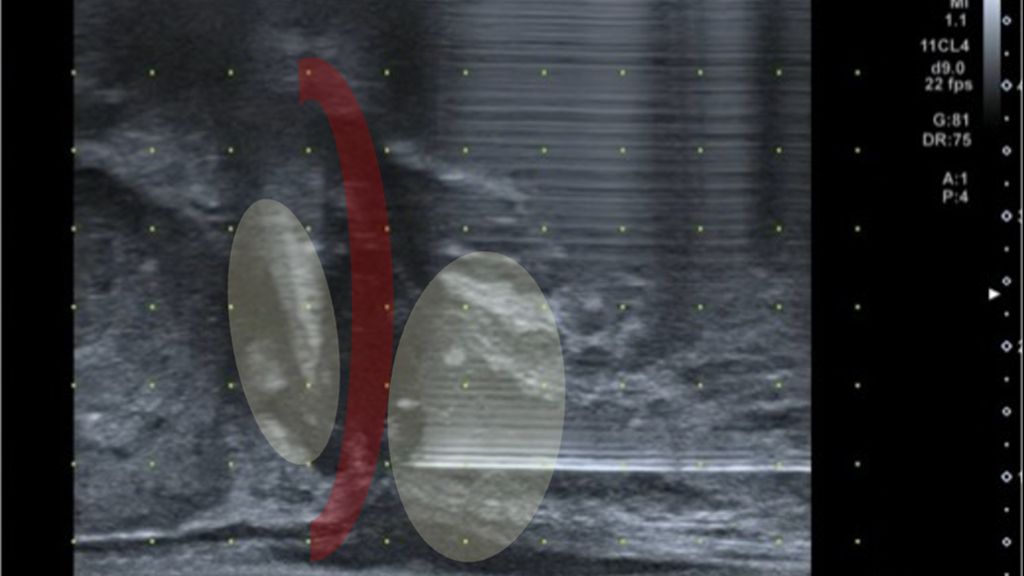

Abb. 2: Sonografische Darstellung der tiefen Beckenbodenmuskulatur (rot) und der Prostataapex. In Gelb dargestellt sind die Applikationsorte der tiefen Lokalanästhesie vor perinealer Prostatabiopsie